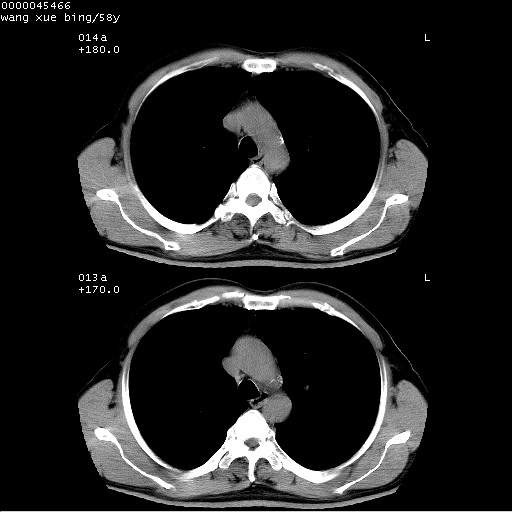

患者 男,58岁。咳嗽、咯血3月余。

胸部ct轴位平扫(层厚10mm,螺距1.5,重建间隔10mm),图像如下:

考虑右下肺中心型肺癌并远端阻塞性炎症及胸膜及纵隔淋巴转移

右肺下叶周围型肺癌伴空洞形成!征象比较明显!分叶、毛刺、胸膜凹陷征、厚壁空洞,壁结节!

影像符合癌性空洞表现,临床如无咳大量浓臭痰史,还是考虑周围型肺癌可能性大。

空洞壁厚,不规则,其内可见壁结节,周围可见毛刺及阻塞性炎变,多考虑癌性病变.